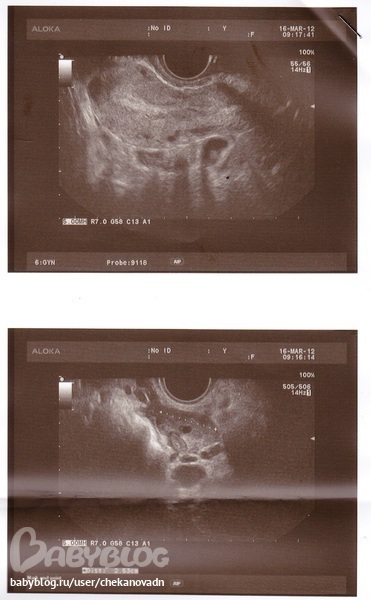

УЗИ малого таза

ФолликулометрияПланирую беременность, ходила на УЗИ сегодня (23 день цикла). Вопрос был по поводу рубца на матке (10 месяцев назад было кесарево), сказали все хорошо. Вот заключение, прокомментируйте, пожалуйста!

P.S.: В правом яичнике желтое тело - это значит, что была овуляция?? Если честно ниче в этом не понимаю